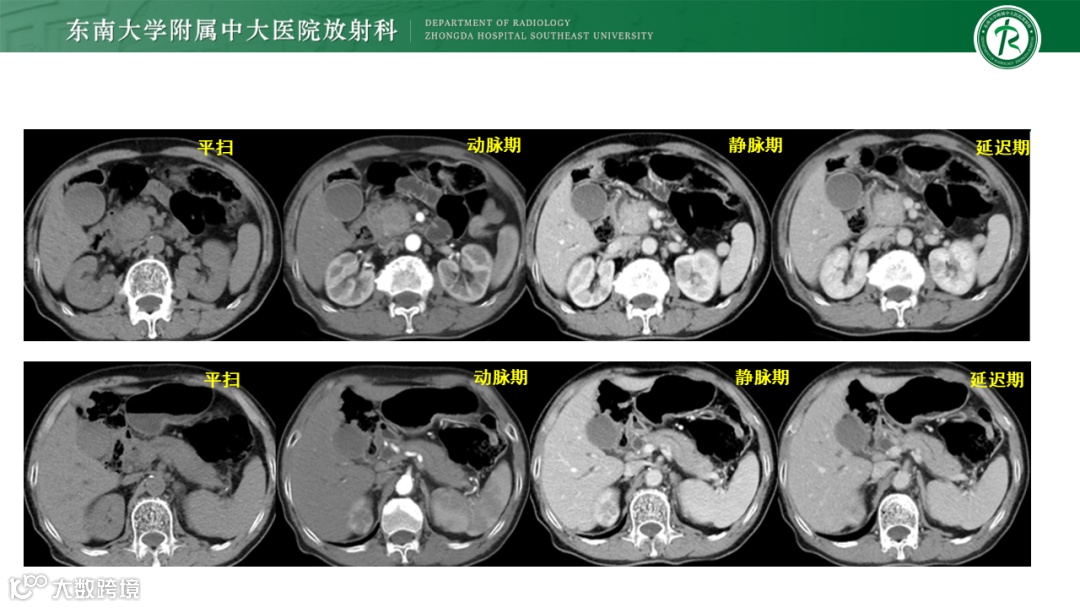

病例1:胰腺导管腺癌-高中分化

病例2:1)炎性肌纤维母细胞肿瘤 2)局限性非肿瘤性病变,如IgG4相关性硬化性疾病 3)韧带样纤维瘤病待排

病例3:胰腺导管腺癌

病例4:IgG4自身免疫性胰腺炎